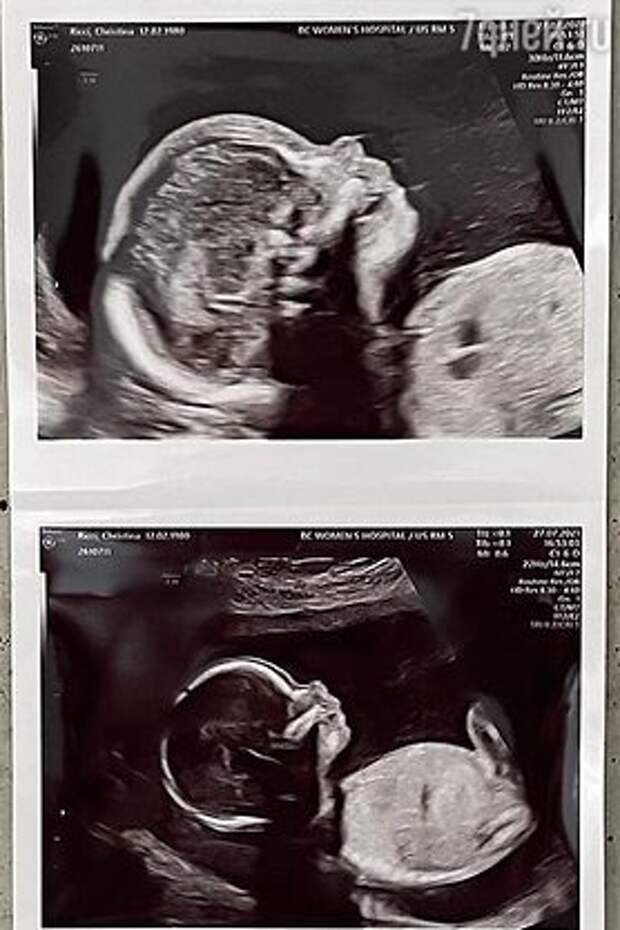

Теперь она совершенно счастлива и ждет от своего бойфренда ребенка. Об этом Риччи сообщила на своей страничке в Инстаграме. Актриса сделала это, опубликовав сонограмму своего пока что не родившегося малыша. А подписала она ее так:«Жизнь становится все лучше!»

О том, кто является отцом будущего ребенка 41-летней актрисы, стало известно сразу же после публикации Кристины. Это произошло, когда известный стилист Марк Хэмптон разместил на своей страничке целую серию сонограмм, включавшую фото со странички Риччи. И пояснил, что «папочка» — именно он.